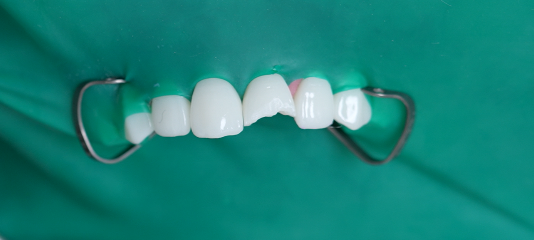

2025.05.12

코어가 완전히 경화된 후

신경치료를 진행합니다.

러버댐 착용 예시 사진

우선 코어 제작으로

러버댐을 활용하여 외부 오염을 차단한 후

신경치료를 실시하면

감염 위험도 줄어듭니다.